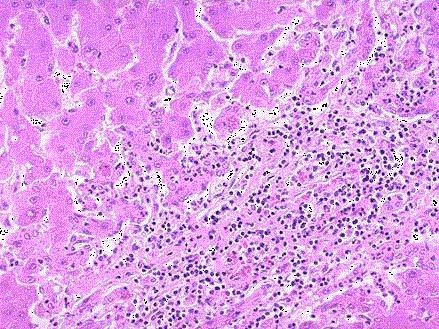

问题 患者,33岁,男性,厌食,进行性消瘦伴右上腹疼痛1个月。肝穿刺组织病检,镜下观如图,可见何种病变 ( )

选项 A.假小叶形成 B.肝细胞水肿 C.碎片状坏死 D.点状坏死 E.大块坏死

答案 C